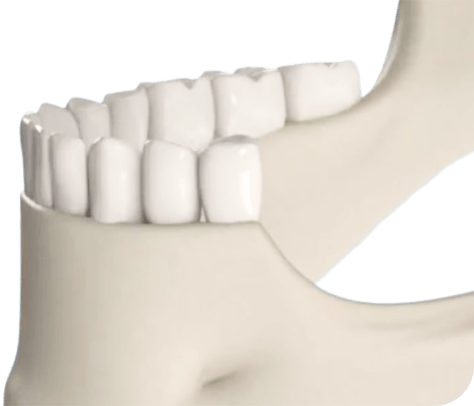

Зубов нет совсем

Не можете нормально питаться, стыдно общаться с людьми.

- Подходит при атрофии кости

- Самое быстрое решение при множественном и полном отсутствии зубов и атрофии кости — все зубы за 8 часов.

- Протез надёжно держится во рту, не вызывает рвотного рефлекса

- Улучшение дикции, омоложение контура лица

- Минимум противопоказаний, не требует наращивания костной ткани